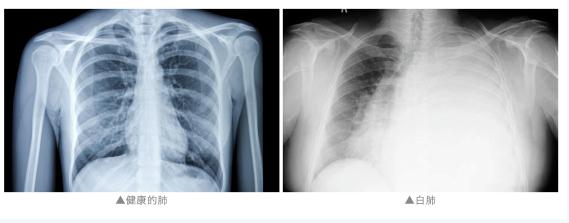

通常来说

“白肺”是指急性呼吸窘迫综合征

主要发生在重症感染时

双肺弥漫性病变进展迅速

其症状和严重程度都与支原体肺炎不同